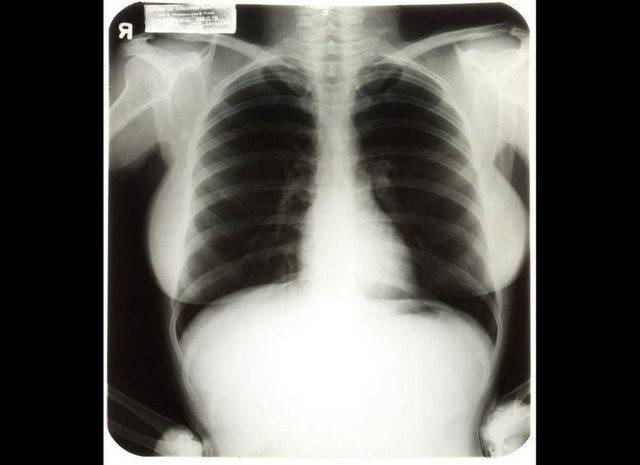

Ondokuz Mayıs Üniversitesi (OMÜ) Tıp Fakültesi Radyoloji Anabilim Dalı öğretim üyesi Prof. Dr. Çetin Çelenk, havaalanı, alışveriş merkezi, kamu kurumları gibi değişik yerlerin girişlerinde güvenlik kontrolü amacıyla bulundurulan X-Ray kapılarından geçmenin sağlık açısından sakıncalı olmadığını söyledi. Prof. Dr. Çelenk, "Özellikle hamile kadınlar, bu kapılardan geçmekten imtina ediyor, geçmek istemiyorlar. Ancak endişe edecek bir durum yok, rahatlıkla geçebilirler" dedi.

OMÜ Tıp Fakültesi Radyoloji Anabilim Dalı öğretim üyesi Prof. Dr. Çetin Çelenk, günümüzde bir çok yerde güvenlik amaçlı sıkça kullanılan metal kapı dedektörleri ile ilgili toplumda yanlış bir algı bulunduğunu dile getirdi. Sıklıkla iki tür güvenlik cihazının bulundurulduğunu bunlardan birinde X ışınının, diğerinde ise elektromanyetik alan kullanıldığını belirten Prof. Dr. Çelenk, şunları söyledi: